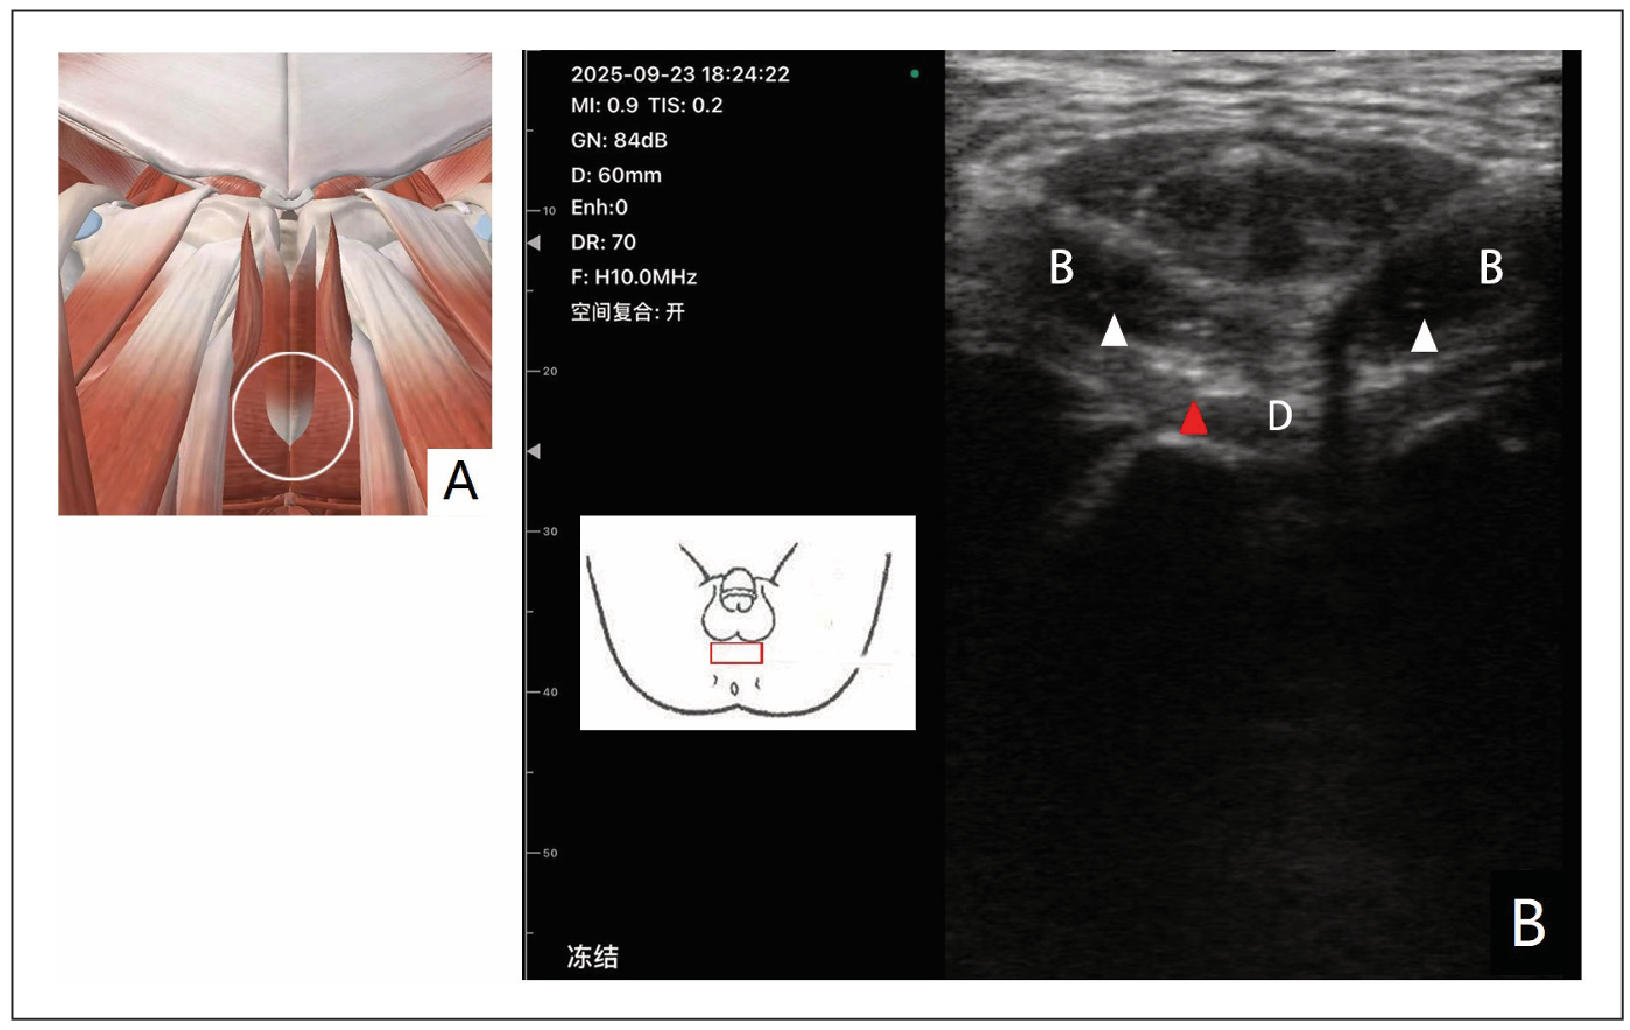

The pelvic floor muscles in the perineal region of CP/CPPS patients also exhibited significant pathological changes under musculoskeletal ultrasound examination. In addition to inflammatory edema, which was similar to that observed in the muscles of the pubic region, we also detected calcification in some patients. The inflammatory edema in the perineal pelvic floor muscles presented as swollen and hypoechoic areas, while the calcification appeared as bright, echogenic foci within the muscle tissue. These echogenic foci represented the deposition of calcium salts, which can occur as a result of chronic inflammation and tissue damage (Figure 2).

Figure 2. Musculoskeletal ultrasound scan in the perineal area (A) schematic diagram of anatomical structure; (B) ultrasound image of perineal muscle; the white triangle refers to the area of inflammation and edema. The white circle represents the anatomical structure of the ultrasound scanning area. The red square represents the placement position of the probe; the red triangle refers to the calcified area. B, Bulbospongiosus; D, Deep transverse perineal

The perineum is a highly sensitive area, and any pathological changes in the pelvic floor muscles in this region can cause severe perineal pain. The inflammatory edema can directly irritate the pain receptors in the perineal skin and underlying tissues, leading to a burning, stinging, or throbbing pain. The calcification, on the other hand, can cause mechanical irritation and compression of the surrounding nerves and blood vessels, further exacerbating the pain. This perineal pain is a common and distressing symptom for CP/CPPS patients, and its direct link to muscle pathology, as revealed by musculoskeletal ultrasound, was previously overlooked. At the same time, some patients complain of numbness or burning symptoms in the perineum due to prolonged sitting, which is closely related to the compression of the perineal nerve at the ischial tuberosity. It is necessary to release this nerve compression point.